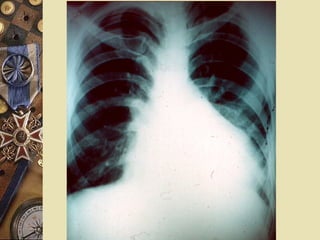

ELECTROCARDIOGRAMAELECTROCARDIOGRAMA

Alternancia eléctrica

 Signo de la

cantimplora